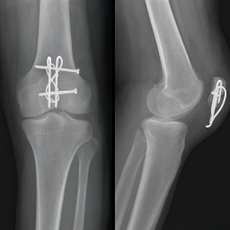

Открытый остеосинтез надколенника

Открытый остеосинтез надколенника — это хирургическая операция для лечения переломов надколенника, при которой делается разрез, костные отломки сопоставляются и фиксируются металлическими конструкциями (спицами, проволокой, винтами), а затем рана закрывается.

Цель — восстановить анатомически правильное положение кости, обеспечить ее надежную фиксацию и ускорить сращение для скорейшего восстановления функции коленного сустава.

Надежная фиксация: хирургическое вмешательство позволяет прочно зафиксировать костные отломки в анатомически правильном положении с помощью специальных металлических конструкций (проволока, спицы, пластины), предотвращая их вторичное смещение.

Восстановление анатомии: операция позволяет точно сопоставить фрагменты кости, восстанавливая правильную анатомию сустава и предотвращая деформации.